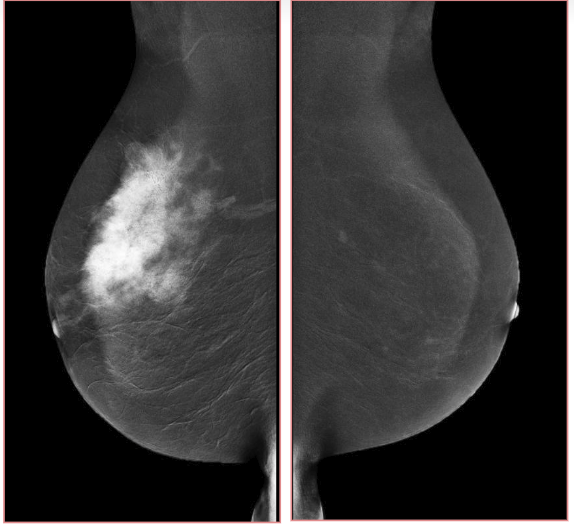

Digital breast tomosynthesis (DBT) is a promising new technology for acquiring and displaying three-dimensional mammograms [17]. Because of its improved ability to differentiate true breast lesion or summation of normal breast structures. An example image of tomosynthesis is shown in Fig. 3, for the different planes, it has improved characterization of masses. Tomosynthesis is increasingly being used in the diagnostic setting to evaluate masses, asymmetries, and architectural distortion. Tomosynthesis can be done in full or spot compression views as needed [18]. The sensitivity and specificity of DBT ranged from 74.2% to 86.9% and 97.0% to 97.5%, respectively [19].